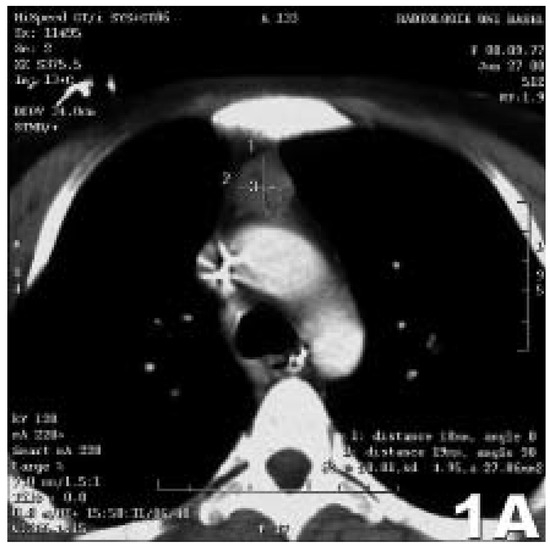

Case Report

Life-threatening myasthenia gravis masked by a psychiatric disorder

by Stephan J. Rüegg, S. Dirnhofer, C. H. Buitrago-Tellez, A. J. Steck and S. Marsch

Swiss Arch. Neurol. Psychiatry Psychother. 2007, 158(4), 150-154; https://doi.org/10.4414/sanp.2007.01850 - 1 Jan 2007

Cited by 4 | Viewed by 62

Abstract

The coincidence of a psychiatric and a neurological disorder in the same patient may be an especially challenging clinical situation [...] Full article

Show Figures

Figure 1